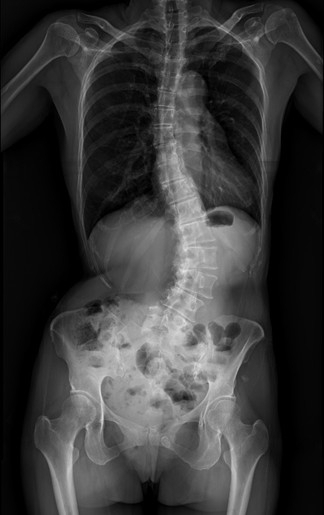

【記者張原銘、張皓傑台中報導】55歲的黃小姐年輕時即被健檢醫師提醒有脊椎側彎,但多年來未加以治療。近兩年症狀明顯惡化,出現劇烈腰背疼痛、下肢麻痺與腫脹,夜間常因疼痛難以入眠,甚至影響行走能力與工作生活品質。經友人推薦,黃小姐前往臺中市立老人復健綜合醫院(簡稱中醫大市醫)骨科就醫,經微創脊椎中心助理副院長張建鈞醫師評估後,決定接受3D導航微創脊椎矯正手術。術後脊椎側彎角度由47度矯正至10度,身高增加約5公分,困擾長達25年的病痛大幅改善,終於能安穩入睡。

共同執行手術的骨科部副部長林琮凱醫師表示,脊椎側彎(Scoliosis)並非單純姿勢不良,而是脊椎向側面異常彎曲,並伴隨椎體旋轉變形。臨床上以Cobb角度作為診斷依據,超過10度即可確診。若長期未妥善處理,可能引發慢性疼痛、神經壓迫,甚至影響心肺與內臟功能。常見類型包括幼年型、非特異型、退化性與神經肌肉型,其中退化性脊椎側彎多好發於中老年族群,因進展緩慢而容易被忽略。